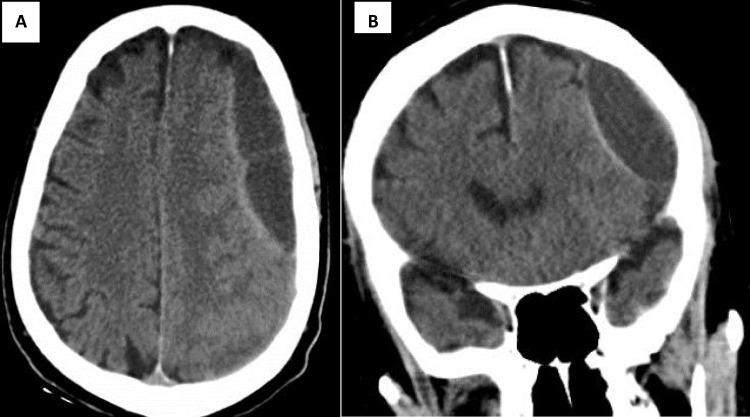

New oral anticoagulants (NOACs) have become more popular in the last few decades. Although apixaban has been proven to be safer than warfarin and causes less hemorrhage in comparison to other NOACs, it still poses a risk of spontaneous bleeding. We present here an 81-year-old male known case of heart failure with reduced ejection fraction (HFrEF) associated with an apical thrombus of 0.93×1.29 cm who presents with cognitive decline, slurred speech, and right side weakness following apixaban use for his apical thrombus. On further evaluation of non-contrast brain (), there was a large extra-axial subacute subdural hematoma with thick septations in the left parietal region, measuring 2.6 cm in thickness, causing an a mass effect, and an a midline shift of 1 mm. Following neurosurgery, cardiology, and anesthesiology discussions, the surgery was deferred due to his age and coexisting conditions with regular follow-ups. The patient has now gained full consciousness and is currently undergoing physiotherapy. This case highlights an elderly patient with apixaban-induced subdural hemorrhage, which is a rare entity in the medical literature. Although apixaban is safer than other NOACs, it may cause subdural hemorrhage.

在过去几十年中,新型口服抗凝剂(NOACs)越来越受欢迎。尽管已证实阿哌沙班比华法林更安全,与其他NOACs相比出血更少,但它仍有自发性出血的风险。我们在此介绍一名81岁男性,已知患有射血分数降低的心力衰竭(HFrEF),伴有0.93×1.29 cm的心尖血栓,在使用阿哌沙班治疗心尖血栓后出现认知衰退、言语不清和右侧肢体无力。在进一步评估非增强脑部()时,左顶叶区域有一个巨大的轴外亚急性硬膜下血肿,有厚分隔,厚度为2.6 cm,产生占位效应,中线移位1 mm。经过神经外科、心脏病学和麻醉学讨论后,由于患者年龄和并存疾病,手术延期,并定期进行随访。患者现已完全清醒,目前正在接受物理治疗。该病例突出了一名老年患者发生阿哌沙班诱导的硬膜下出血,这在医学文献中是一种罕见的情况。尽管阿哌沙班比其他NOACs更安全,但它可能导致硬膜下出血。